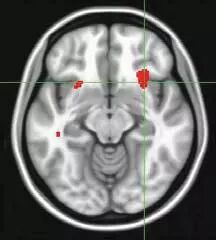

如果病人在治疗之前,大脑的前脑岛(大脑的右侧)区域在静息状态下的活跃程度较低(如图红色部分区域,绿色十字锁定的部分),这表示认知行为治疗对抑郁症有明显的缓解作用;相反,脑岛过度活跃则可以预测草酸艾司西酞普兰对抑郁症具有缓解作用。

大脑的PET扫描可以优先预测哪种治疗(抗抑郁药物、心理治疗)对患者抑郁症的疗效更好。静息状态下脑岛右前部活动水平较高,显示了认知行为疗法对患者作用不显著(CBT NR),而服用艾司西酞普兰的患者症状有所减轻(sCIT REM);相反当脑岛活动水平低时,显示CBT疗法治疗有效(CBT REM),而服用艾司西酞普兰的患者症状缓解不明显(sCIT NR)(见上图)。